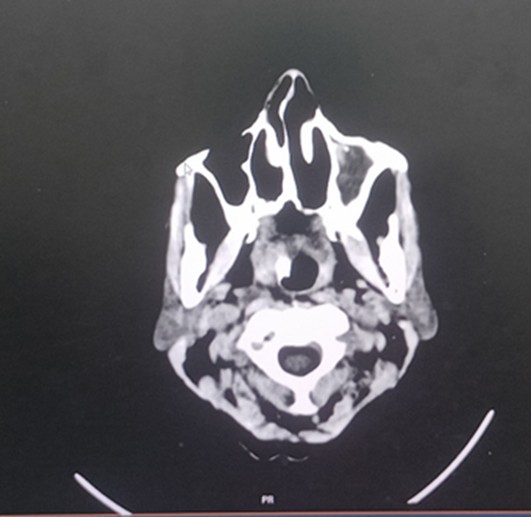

CT brain – 20.2.25

Acute non-hemorrhagic infract in left MCA territory

Age related Atrophy

CT brain – 21/2/25

Sub-Acute infract in left MCA territory infract with grade 2 hemorrhagic transformation mass effect with no significant midline shift